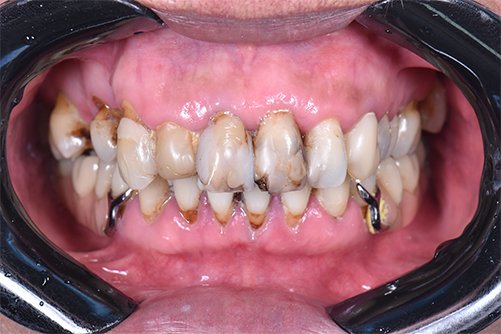

No caso clínico relatado a seguir, é apresentada a reabilitação de uma paciente do gênero feminino, de 45 anos, com o desejo de melhorar o aspecto do seu sorriso. Durante o exame clínico inicial, foi verificada a presença de exposição gengival maxilar excessiva durante o sorriso espontâneo, associada à desalinhamento dentário e presença de restaurações extensas e insatisfatórias nos dentes anterossuperiores (Figuras 1 e 2), além de mobilidade dos dentes 15 ao 25. Ao exame radiográfico, foi observada extensa perda óssea periodontal, além de lesões de cárie/perda de estrutura coronária nos dentes 13 a 23, 15, 24 e 25 (Figura 3), sendo indicada a exodontia desses elementos, seguida da instalação de implantes osseointegráveis.